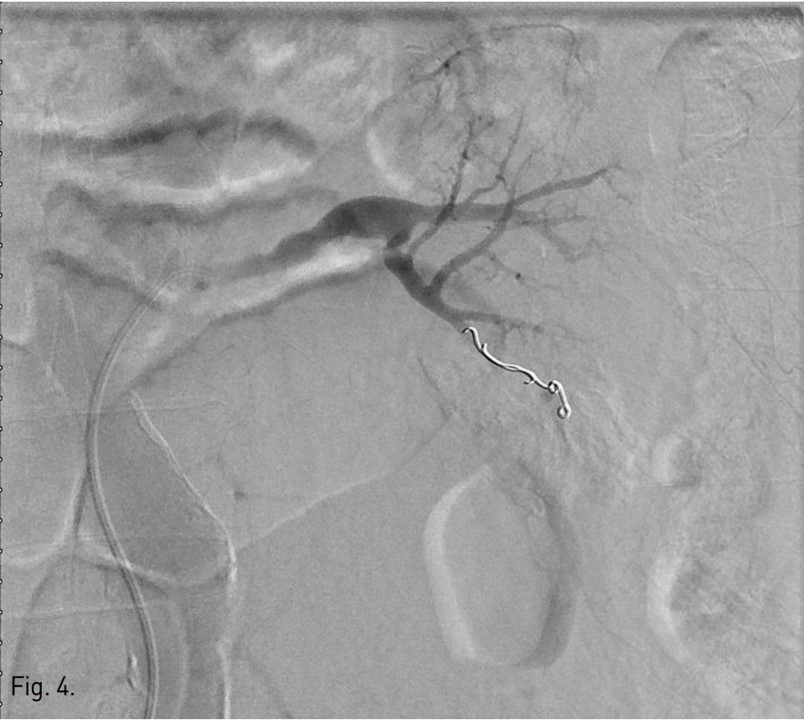

우측 총대퇴동맥을 천자하여, 5Fr sheath(Terumo, Tokyo, Japan)를 통해 5Fr Cobra catheter(Cook, Bloomington, USA)를 좌측 신동맥 기시부에 위치하여 혈관조영술을 시행하였다. 좌측 콩팥의 하극 부위 콩팥동맥 분지에서 조영제 누출이 있었다(Fig. 3). Microcatheter(Stride, Asahi Intecc co., Japan)로 출혈이 있는 신동맥 분지를 선택하여 microcoils (3x2mm, Tornado embolization microcoil, Cook, Bloominton, USA) 3개와 gelatin sponge particles (Gelfoam, Upjohn, Kalamazoo, MI, USA)을 이용하여 색전술을 시행하였다. 이후 시행한 혈관조영술에서 더 이상의 조영제 누출이 보이지 않아 시술을 종료하였다(Fig, 4). 이후 8개월 뒤 추적 전산화단층촬영에서 좌측 콩팥주위 혈종은 매우 크기가 감소하였다(Fig. 5).

Fig. 4.

Fig. 4. Left renal angiography after embolization using microcoils and Gelfoam shows no more contrast extravasation.